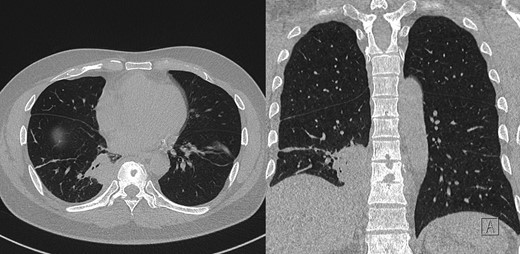

Computerized tomography (CT) demonstrated right lower lobe consolidation and parapneumonic effusion. He was treated with piperacillin/tazobactam and methotrexate ceased. In the subsequent months he represented for recurrence of the same symptoms. CT showed the persisting effusion despite further antibiotic therapy.

During this period he also developed osteolytic lesions of the T9/10 vertebral bodies immediately adjacent to the effusion (Fig. 1). Magnetic resonance imaging (MRI) was arranged showing T8–T10 spondylodiscitis, prevertebral and epidural phelgmons (Fig. 2), without radiological evidence of spinal cord compression. Further imaging with gallium scan showed no evidence of osteomyelitis elsewhere in the body, but unexpectedly revealed area of increased vascularity in the right iliac fossa suggestive of soft tissue infection. CT abdomen confirmed the lesion to be a peri-appendicular abscess (Fig. 3).

Post-contrast CT chest, showing ostelytic lesion of T9 vertebral body developed since original presentation and imaging. Adjacent to T9 vertebral body is area of persistent parapneumonic effusion.